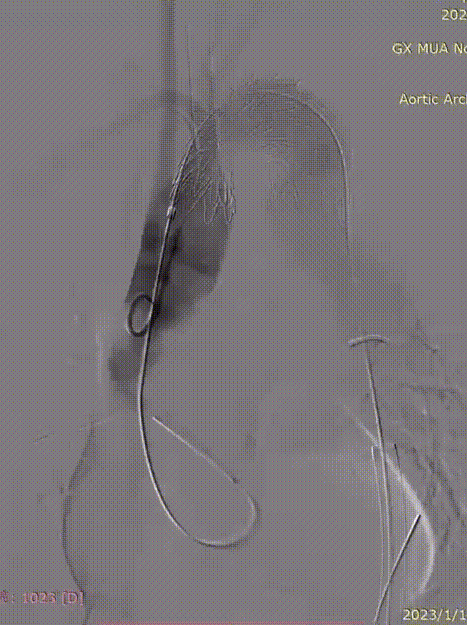

释放主体

技术优势:由于弓形陡峭,瘤腔巨大,支架需要硬导丝支撑到大弯侧,才能确保在释放时保持在原位不移动。

通过分段释放及办法,将支架远端先行释放,填塞瘤腔,可以提供更稳定的支撑力,确保在支架释放时的准确性。

远端释放之后,支架近端仍固定在输送杆上,可以在释放支架近端的过程中适当微调头端的位置。

gore医疗怎么样「胸有乾坤」化险为夷,通险畅机——GORE® TAG® 胸主动脉覆膜支架治疗累及异形弓部动脉瘤_https://www.jmylbn.com_新闻资讯_第20张

顶导丝让支架贴紧大弯侧血管壁

gore医疗怎么样「胸有乾坤」化险为夷,通险畅机——GORE® TAG® 胸主动脉覆膜支架治疗累及异形弓部动脉瘤_https://www.jmylbn.com_新闻资讯_第21张

分段释放支架